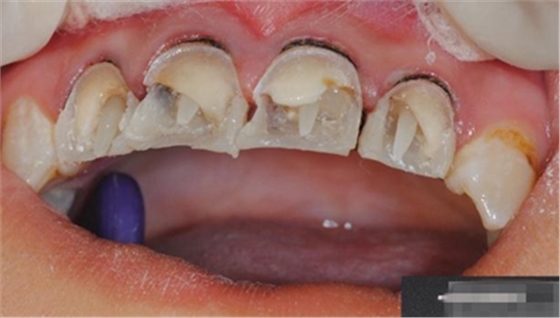

【檢查】12,11,21,22,均行玻璃離子充填,各牙不同程度部分充填物脫落,探(—),叩(—),冷刺激無(wú)反應(yīng),無(wú)松動(dòng),牙齦顏色粉紅,質(zhì)地堅(jiān)實(shí)而有彈性,點(diǎn)彩正常,牙結(jié)石(—);牙髓活力測(cè)試無(wú)反應(yīng)。

【診斷】12,11,21,22牙體缺損

【口內(nèi)簡(jiǎn)單充填】臨時(shí)充填 可以玻璃離子 也可以樹(shù)脂(不涂布酸蝕、粘結(jié)劑)